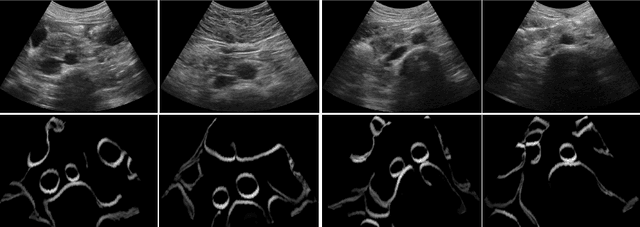

Abstract:Anatomical segmentation of organs in ultrasound images is essential to many clinical applications, particularly for diagnosis and monitoring. Existing deep neural networks require a large amount of labeled data for training in order to achieve clinically acceptable performance. Yet, in ultrasound, due to characteristic properties such as speckle and clutter, it is challenging to obtain accurate segmentation boundaries, and precise pixel-wise labeling of images is highly dependent on the expertise of physicians. In contrast, CT scans have higher resolution and improved contrast, easing organ identification. In this paper, we propose a novel approach for learning to optimize task-based ultra-sound image representations. Given annotated CT segmentation maps as a simulation medium, we model acoustic propagation through tissue via ray-casting to generate ultrasound training data. Our ultrasound simulator is fully differentiable and learns to optimize the parameters for generating physics-based ultrasound images guided by the downstream segmentation task. In addition, we train an image adaptation network between real and simulated images to achieve simultaneous image synthesis and automatic segmentation on US images in an end-to-end training setting. The proposed method is evaluated on aorta and vessel segmentation tasks and shows promising quantitative results. Furthermore, we also conduct qualitative results of optimized image representations on other organs.